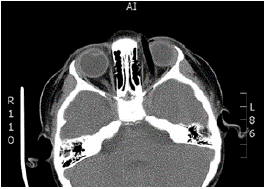

The tomography showed an intraorbital route of the foreign body towards the right side, and above the left eyeball towards the temporal lobe; no intraconal or intraocular lesions were evident, and no intracranial, subdural or epidural hematomas or retroconal bleeding were observed (Figures 1 and 2).

Intraorbital foreign body.

Figure 1: Intraorbital foreign body.

Source: Document obtained during the study.